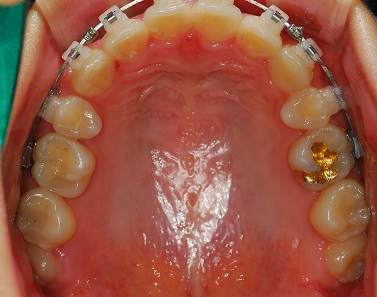

교정 전 치아 교정 후 치아

이제 보니 확실히 비교가 되네요!

뻐드러 졋던 이가 많이 들어갔어요